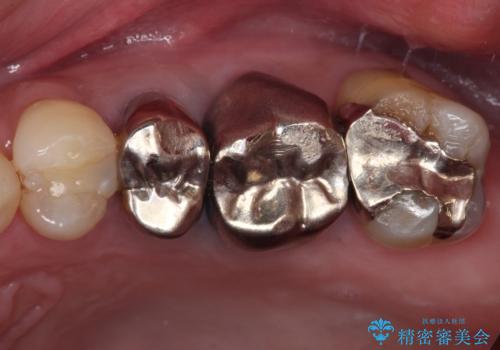

- 頻繁に銀歯が外れてしまうとのことで来院された患者様です。

歯肉の中、深いところまでむし歯が進行しており、歯根を部分矯正で引っ張り出してから補綴治療を行うか、抜歯してインプラント補綴治療を行うか選択することになりました。

海外での勤務があり、部分矯正は困難とのことで、インプラントによる補綴治療を行うこととしました。